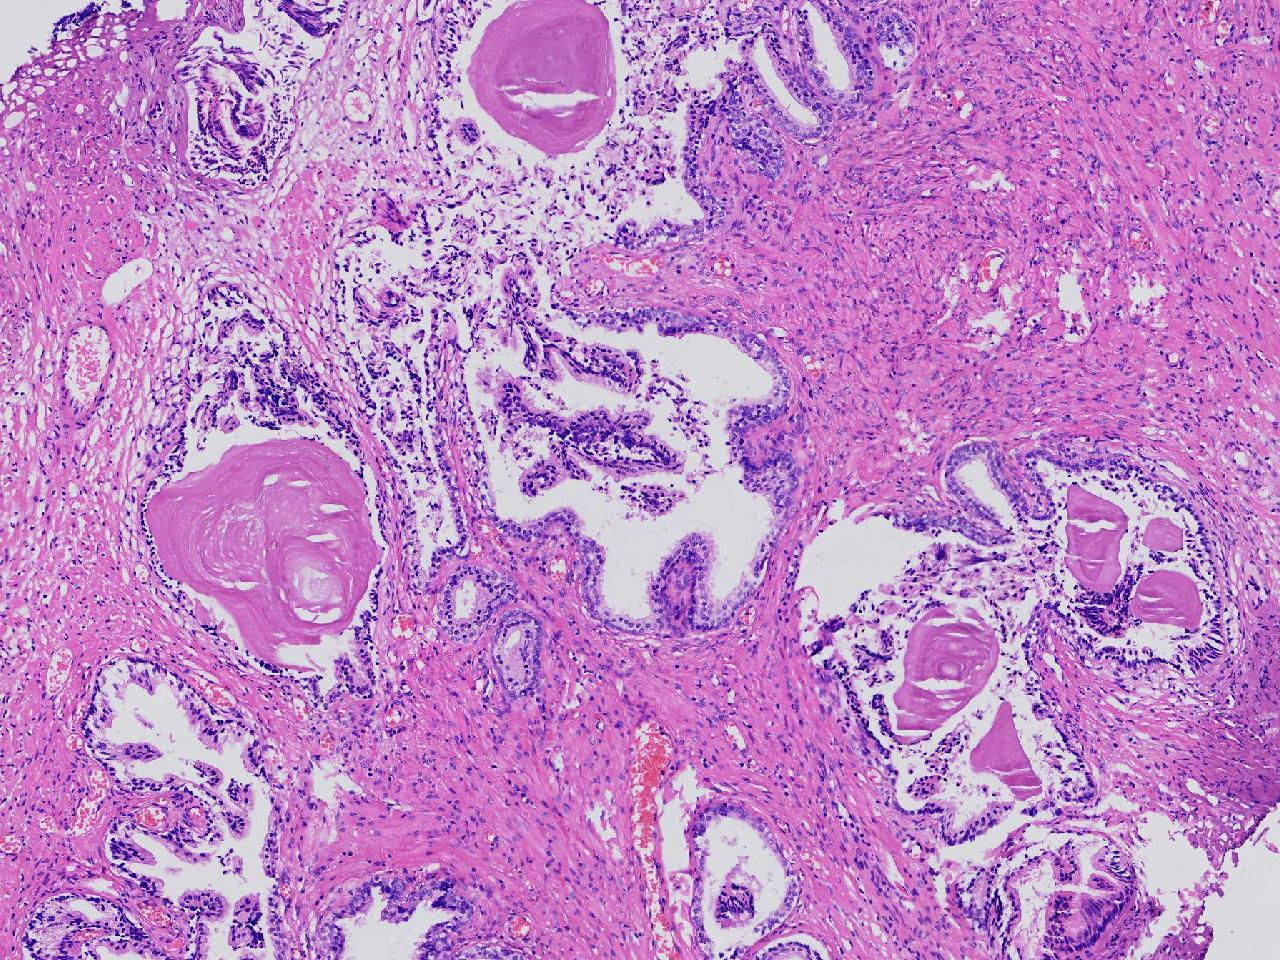

良性前列腺增生?

男,68岁,排尿困难半年余。行前列腺前切术。

前列腺电切标本

灰粉色条索状软组织多块,4X3X3厘米。

考虑为良性前列腺增生症

良性增生

BPH.